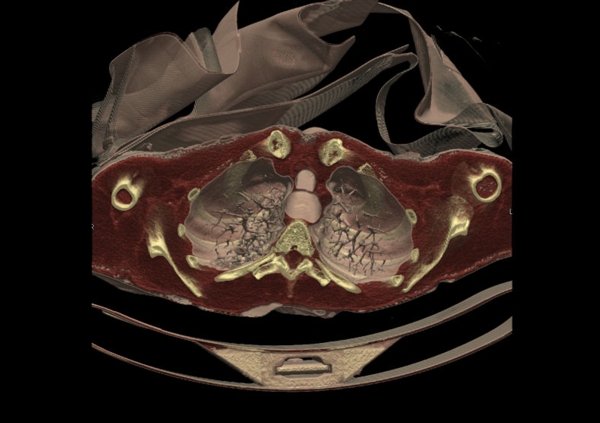

在随后的幻灯片中,您将看到来自瑞典医学图像科学与可视化中心(the Center for Medical ImageScience and Visualization ,CMIV)的Anders Persson和他的同事们运用CT,MRI和超声得到的令人惊叹的尸检图片。这些图片描绘了人体骨骼,消化道,循环系统和大脑以及野猪的前端结构。

4, 人体,横切;骨骼,肌肉组织,器官和肺脏清晰可见。